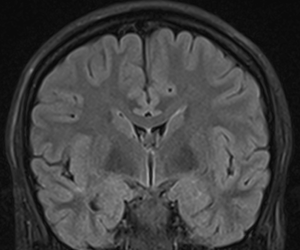

[[Fil:PostCorSylvii.png| | [[Fil:PostCorSylvii.png|300px|thumb|right|Fig.6 Et coronalt MR snit gennem den posteriore del af fissura Sylvii hvor temporallappens øvre flade er plan]] | ||

Den superiore flade af temporallappen grænser op mod Insula inferiore halvdel. Den forreste del af denne flade er konkav (planum polare) og matcher den anteriore inferiore konvekse form af Insula, mens den posteriore supriore flade en med plan (planum temporale). Denne forskel kan tydligt erkendes på coronale MR-skanningssnit (Fig. 5+6). Overgangen mellem den konkave og den plane den af temporallappens superiore flade markere lokalisationen af Heschel's gyrus. Heschel's gyrus har et skråt forløb fra antero-lateralt til postero-medialt. Lateralt findes Heschel's gyrus lige overfor gyrus postcentral i parietallappen adskilt af lateralfissuren. Følges Heschel's gyrus medialt posteriort peger den mod atrium af ventrikelsystem lige posteriort for thalamus (Fig. 4).